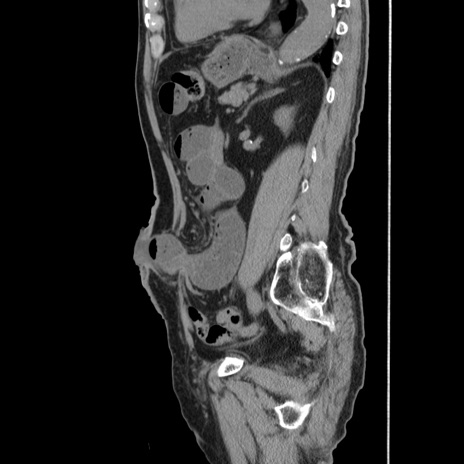

症例24(矢状断像)

【症例】80歳代男性

【主訴】左側腹部痛、嘔吐

【現病歴】本日早朝より左腹部に痛みあり。昼頃嘔吐認めたため、救急要請。

【既往歴】直腸癌(Mile手術)、胆摘

【身体所見】意識清明、BT 35.9℃、BP 221/93mmHg、SpO2 97%(RA) 、腹部:左ストーマ周囲に限局性の腹部膨隆あり。 膨隆部自発痛・圧痛あり・軟。

【データ】WBC 7700、CRP 0.09